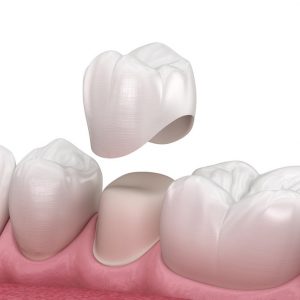

Crowns

A crown is a custom-made porcelain protective layer that goes over the natural tooth. A crown is recommended if you have a weakened tooth from either decay, large fracture or if the tooth has had Root canal treatment, it helps to make the tooth stronger and prevent it from breaking further.